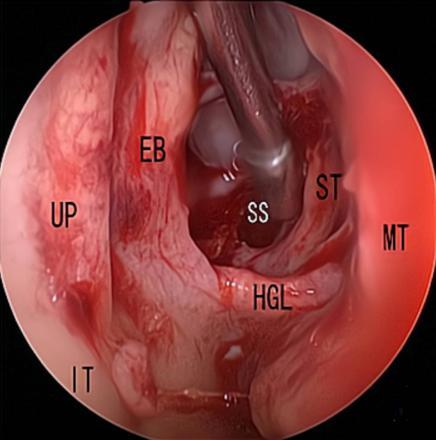

摘要:目的 探究经中鼻甲基板入路的手术技巧及临床效果,旨在系统评估一种兼具良好手术视野和微创性的蝶窦开放径路。方法 回顾性分析2019年9月-2023年9月该院收治的35例孤立性蝶窦病变或单侧蝶窦伴毗邻筛窦受累患者的临床资料,均经中鼻甲基板入路的“四步”程序化操作开放蝶窦。观察手术相关情况和并发症发生情况;采用视觉模拟评分法(VAS)评分,评估头痛和流涕等症状改善情况;采用改良隆德-肯尼迪(MLK)评分,评价术腔恢复状况。结果 所有患者术中保留钩突、中鼻甲和筛泡,26例(74.3%)保留上鼻甲;所有患者均达到临床治愈标准,表现为:术腔引流通畅,黏膜完全上皮化,以及蝶窦开口维持良好开放状态。术后病理显示:蝶窦霉菌病19例(54.3%),蝶窦息肉7例(20.0%),蝶窦黏膜慢性炎症9例(25.7%)。所有患者均未发生严重并发症,仅1例(2.9%)于术后12 d出现中鼻甲创面渗血,经电凝止血后治愈。头痛VAS评分由术前的(4.71±1.66)分,降至术后的(0.83±0.39)分,手术前后比较,差异有统计学意义(t = 13.71,P < 0.01);流涕VAS评分由术前的4.00(0.00,6.00)分,降至术后的0.00(0.00,1.00)分,手术前后比较,差异有统计学意义(Z = -4.47,P < 0.01);手术前后嗅觉减退VAS评分比较,差异无统计学意义(P > 0.05)。MLK评分由术前的4.50(2.00,4.00)分降至1.00(0.00,1.00)分,手术前后比较,差异有统计学意义(Z = -5.20,P < 0.01)。结论 经中鼻甲基板入路蝶窦开放术,严格遵循鼻窦解剖层次,在最大限度地保留鼻腔生理结构的前提下,可获得理想的术野暴露。该术式对于局限于蝶窦及后组筛窦的病变,具有确切的临床疗效。值得应用于临床。